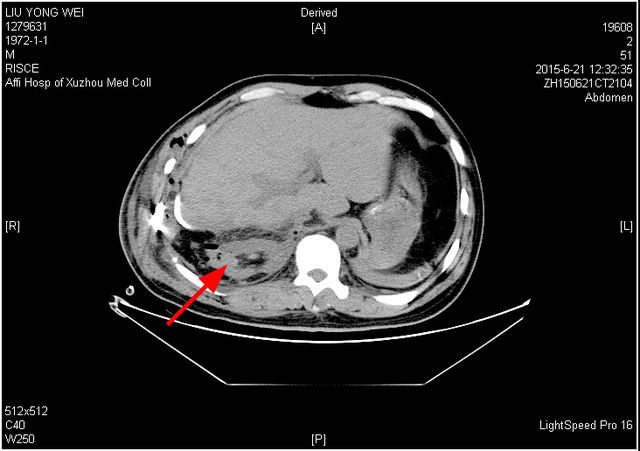

8 I. `! C/ X" Z( I- ~5月5日晨,安徽网曝出题为“宿州男子在徐州做胸腔手术出院第二天右肾失踪”的新闻。当日徐州医学院附属医院即作出回应,并发布患者术后第一日和第五日复查CT的图片,影像中右肾确在腹部相应位置。, u$ Q# i$ U4 C% O% r/ M  P

术后第五日患者的右肾。图:新浪% g! ^, f( p/ O' E

现在大家大概能够理解,医生并没有切除患者肾脏的“动机”。结合徐州医学院附属医院提供的CT证据和手术记录,我们知道了,右肾一直在患者体内。最初的手术当中,医生将受外伤移位的右肾送回至腹腔,并缝合上胸腔和腹腔之间的破口。只不过,在术后的两个月中,患者的右肾慢慢萎缩了,以至于此后几番影像检查中看不到右肾的影像。9 d* j4 `3 J7 x0 u! l6 V5 g